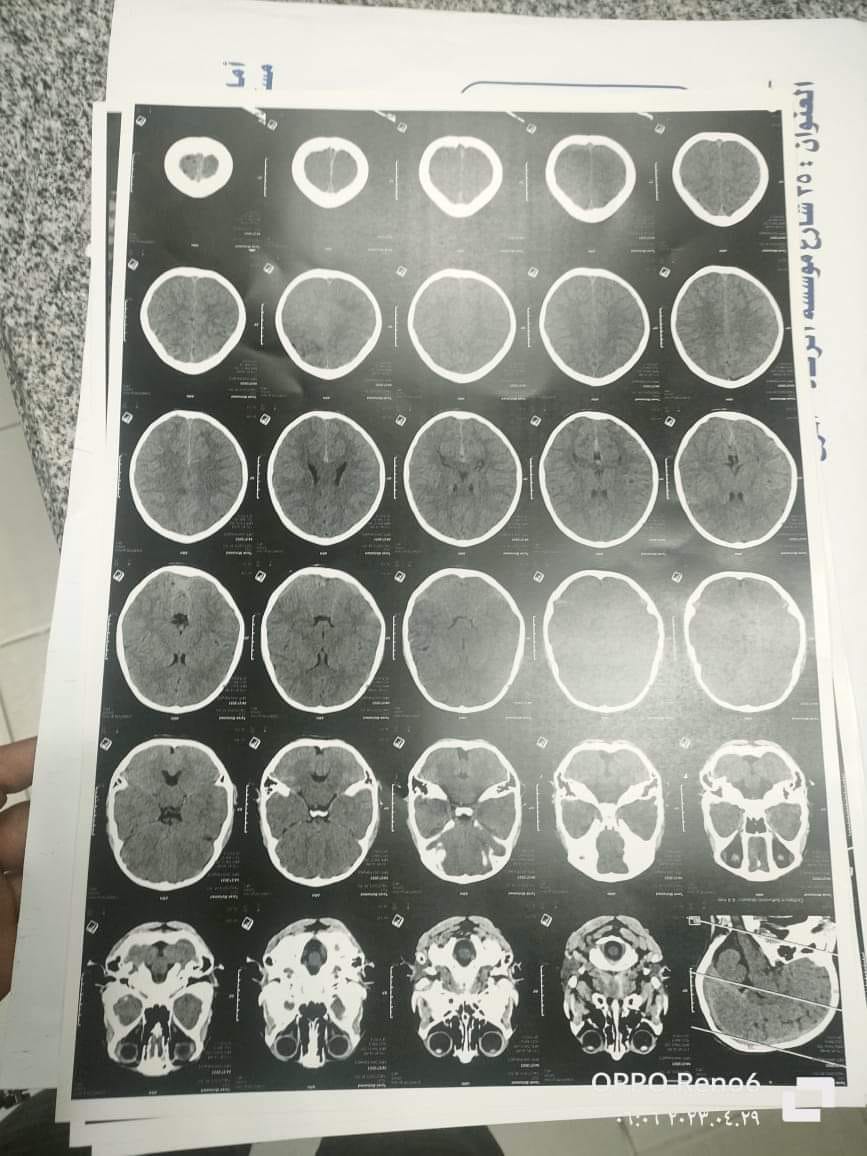

سلمت الأسرة الطفل للتمريض، ودخل غرفة العمليات، وبعد 7 دقائق فقط، وقبل بدء العملية، حسبما وصفت مروة، بدأ كل شيء ينقلب رأسًا على عقب، وكُثرت حركة الأقدام في جميع الأرجاء، وعلمت الأسرة فيما بعد أن التخدير أدى إلى ردّ الطعام الذي تناوله طارق قبل الجراحة، مرة أخرى إلى الرئتين، وتسبب في غلق القصبة الهوائية، ومن ثم توقف عضلة القلب، ونقص أكسجين المخ، وعلى إثر ذلك، يمكث الصغير في غيبوبة تامة منذ أكثر من 20 يوما.

طارق حاليًا في غرفة العناية المركزة، بين يدي الله، وهي العبارة المتكررة، التي يقولها الأطباء للأسرة المنهكة، لأن الطفل بعد تعرضه لإهمال طبي، حتى وإن تمت إفاقته من الغيبوبة، ستبدأ رحلة معاناته مع نتائج نقص الأكسجين في المخ، والتي تسبب إما شللًا كاملًا أو جزئيًا، أو ضمور بالعضلات.